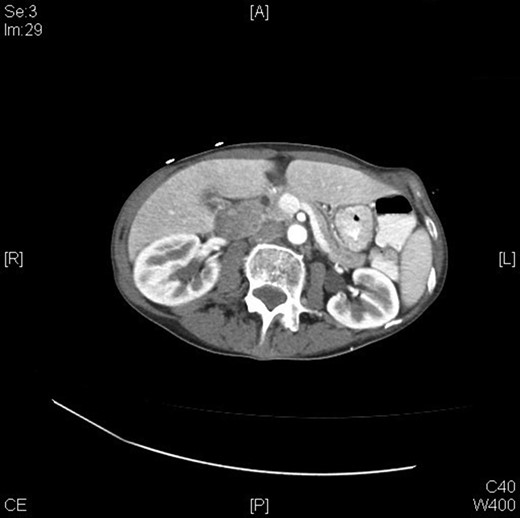

A 70-year-old female presented to the emergency department with complaints of diarrhea, vague, dull abdominal pain, unintentional weight loss and poor appetite. No hematochezia or melaena stated. Fecal occult is strongly positive in the ED. No endoscopies were found in her records. PMHx included COPD, osteoarthritis and DVT. Significant physical exam findings included mild, diffuse abdominal tenderness and RUQ palpable mass, and normal bowel sounds. Labs were significant for a hemoglobin of 5.7, hematocrit of 18.6% and CEA of 29.6. An abdominal/pelvis CT exhibited a 6 cm circumferential mass of the hepatic flexure (Figs 1–3). Two days later, a right hemicolectomy with en bloc pancreaticoduodenectomy was performed. Pathology showed adenocarcinoma stage IIIc (Figs 4–10). Post-operatively, an abdominal/pelvis CT showed bilateral pulmonary emboli and a 14 cm pelvic abscess. Bilateral lower extremity ultrasound showed low probability for DVT. Exploratory laparotomy was performed where the pelvic abscess was seen and extensive lysis of adhesions, resection of ileocolonic anastomosis for contained leak and ileostomy performed. Approximately 4 months after discharge, the patient passed away while in a long-term care facility.

A 2013 study showed that patients who are appropriate for right hemicolectomy with en bloc pancreaticoduodenectomy have the following characteristics: ‘(i) no distant metastasis, (ii) R0 resection being possible on the basis of the preoperative examination, (iii) the patient’s condition being good enough to accept radical multivisceral resection and (iv) the surgical team being experienced enough to perform the procedure’ [10]. Preoperative evaluations are strongly recommended to ensure that patients qualify. Preoperative staging is also a key factor; this is done through abdominal CT scans. CT scans have a significant (99%) ability to detect liver metastases, moderate ability to reveal cT4 stage (86%) cancers but are poor at detecting peritoneal carcinomatosis [10]. CTs are able to distinguish colonic tumor stages pre-operatively and can show invasion through the muscularis propria, indicating stage T3/T4 [10].